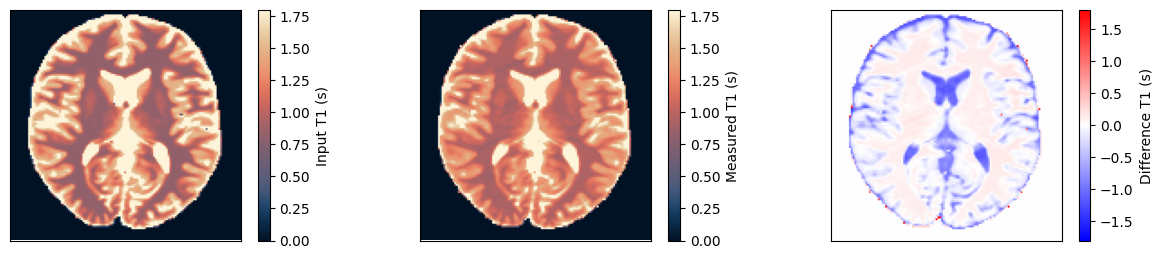

Estimate the T1 maps#

We use a dictionary matching approach to estimate the T1 maps. Afterward, we compare them to the input and ensure they match.

dictionary = DictionaryMatchOp(MOLLI(ti=torch.as_tensor(ti, dtype=torch.float32)), index_of_scaling_parameter=0)

dictionary.append(

torch.tensor(1.0), torch.linspace(0.1, 5.0, 1000)[None, :], torch.linspace(0.1, 5.0, 1000)[None, None, :]

)

m0_match, c_match, t1_match = dictionary(idata.data)

t1_input = np.roll(rearrange(phantom.T1.numpy().squeeze()[::-1, ::-1], 'x y -> y x'), shift=(1, 1), axis=(0, 1))

obj_mask = np.zeros_like(t1_input)

obj_mask[t1_input > 0] = 1

t1_measured = t1_match.numpy().squeeze() * obj_mask

fig, ax = plt.subplots(1, 3, figsize=(15, 3))

for cax in ax:

cax.set_xticks([])

cax.set_yticks([])

im = ax[0].imshow(t1_input, vmin=0, vmax=1.8, cmap=Colormap('lipari').to_mpl())

fig.colorbar(im, ax=ax[0], label='Input T1 (s)')

im = ax[1].imshow(t1_measured, vmin=0, vmax=1.8, cmap=Colormap('lipari').to_mpl())

fig.colorbar(im, ax=ax[1], label='Measured T1 (s)')

im = ax[2].imshow(t1_measured - t1_input, vmin=-1.8, vmax=1.8, cmap='bwr')

fig.colorbar(im, ax=ax[2], label='Difference T1 (s)')

relative_error = np.sum(np.abs(t1_input - t1_measured)) / np.sum(np.abs(t1_input))

print(f'Relative error {relative_error}')

assert relative_error < 0.08

Relative error 0.07901443541049957